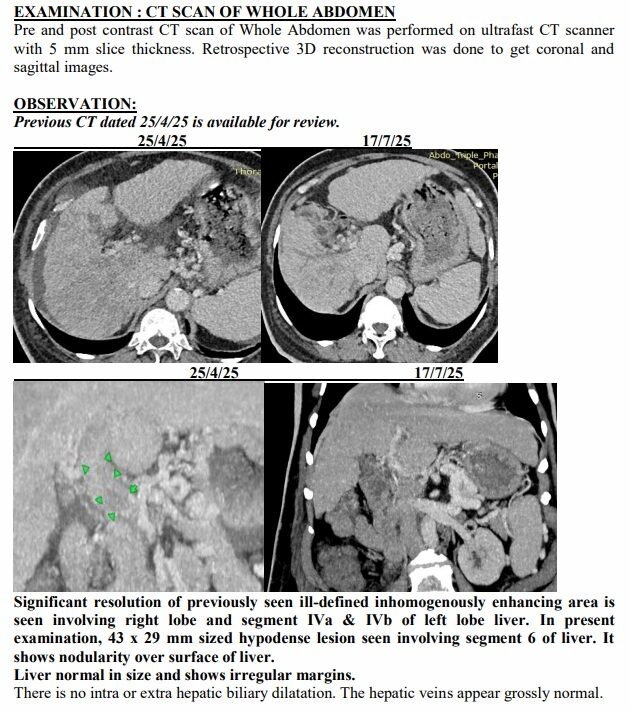

Surat (Gujarat) [India], August 22: On a hot April afternoon in Surat, the Patel family sat in a crowded hospital waiting room, clutching a CT scan report that felt heavier than paper. The words were sharp, merciless: advanced liver cancer, spread across both lobes, blocked veins, fluid buildup, bone changes. For 74-year-old Ravjibhai (name changed), the doctors spoke plainly: there was no cure left, only comfort care.

Yet just three months later, on another afternoon in July, the same family stared at a different scan. The tumours had shrunk to one patch. Blood was flowing again. The swelling was gone. Even the alarming tumour marker that had shot up to 1,000 ng/mL had fallen to 10, back in the safe zone. For a man who had been fading fast, it was a turnaround no one in the room dared to predict.

Ravjibhai’s case became proof of concept. Prescribed a personalised herbal regimen meant to reduce tumour load, restore liver function and boost immunity, he began showing slight changes in weeks. The fever broke. Jaundice eased. He ate a little more each day and walked a little further. His family noticed he was laughing again, something they hadn’t heard in months.

The July scan sealed what they were already feeling at home. The many shadows in his liver had shrunk into one. His abdomen, once swollen with fluid, was flat again. His numbers, which had scared even seasoned oncologists, were suddenly within range.

A senior radiologist who reviewed both reports told this correspondent, “Such a reversal in advanced liver cancer is extremely rare. Clinically, it borders on the unbelievable.”